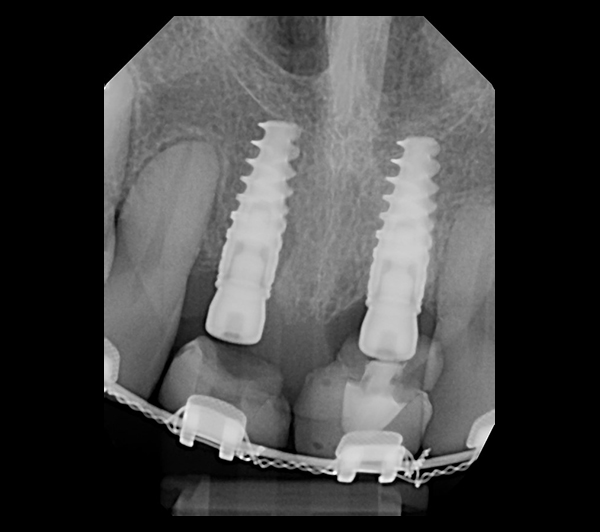

Extraction after forced eruption can allow for a much more favorable implant site compared with extraction alone. This is possible because the tension applied to the periodontal ligament during orthodontic tooth movement stimulates osteoblastic activity to induce new bone formation. As the tooth moves coronally during extrusion, soft tissue and bone attached to the periodontal fibers migrate in the same direction. As a result, forced eruption can be used to enhance the quality and quantity of both hard and soft tissue of future implant sites.

The special report presented below illustrates how orthodontic extrusion was successfully used to improve the periodontal architecture prior to the placement of two adjacent implants in the esthetic zone and thus allowed for a more ideal restorative result.